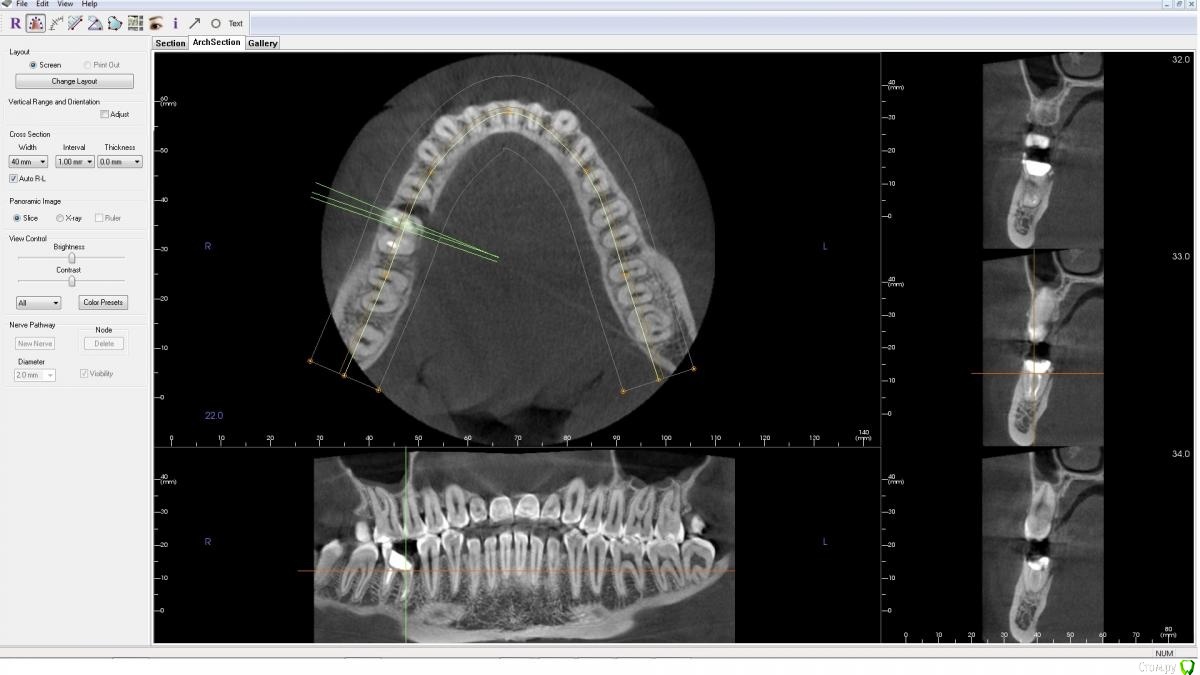

AlenaDM Опубликовано 17 февраля, 2021 Поделиться Опубликовано 17 февраля, 2021 (изменено) Добрый день.Сильно разрушен зуб. Ищу варианты протезирования. Уже посетила нескольких врачей, у всех вариант один - удаление и установка импланта, но возможно кто-то сможет помочь/подсказать другой вариант так сказать, можно ли обойтись "меньшей кровью".КТ из клиники прилагаю (открывается, к сожалению, только в Windows 8 и ниже, формат .exe)Спасибо!https://drive.google.com/file/d/1J0UHeSeCaEhpX65WpDZoImWtN_fYxXUO/view?usp=sharing Изменено 17 февраля, 2021 пользователем AlenaDM Ссылка на комментарий

wladdX Опубликовано 17 февраля, 2021 Поделиться Опубликовано 17 февраля, 2021 На мой взгляд показано удаление. Ссылка на комментарий